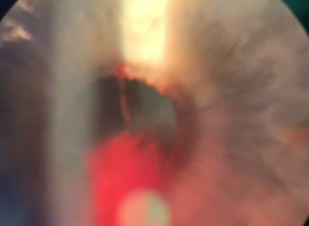

細隙灯検査では、前房に拡大した血液プールが見られ、これは前房水腫として知られる状態だった。

この血液は上瞳孔縁にある「虹彩微小血管腫」より出血していることが確認された。

「出血性虹彩微小血管腫」と診断された。